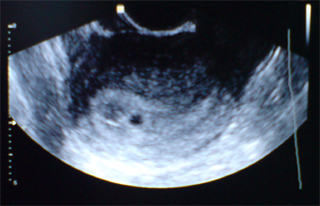

És az ok, amiért nem mutizom nektek, az az, hogy van egy szabályos 6 mms petezsák, benne szabályos szikhólyaggal

Először hasi UHt csinált, de semmit nem látott. Aztán jött a belső

Már rögtön mondta, hogy hát igenigen, ez ott van. Hirtelen úgy megijedtem, hogy arra gondol, hogy a petefészekben van. De aztán már diktálta is az aszisztensnek az adatokat,utána pedig meg is mutatta a képet a kis Mazsolkáról

Olyan aranyos volt az a kis fekete pötty